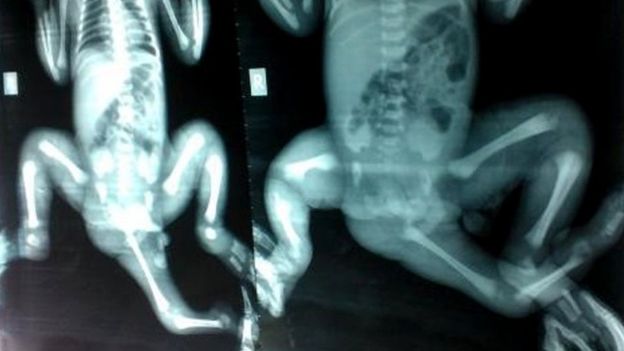

孟加拉国的医生已经切除了部分第三条腿,“但在骨盆部位仍然还有一大块残留组织介于两条正常大腿之间,”Kimber博士说道。

“因为在那儿有一个双胞胎,她有两个直肠、两个阴道,可能还有两个肛门——骨盆部位将会生长发育成为一个非常畸形的双位区。”

他们切除了遗留下来的那部分第三条腿并进行了骨盆局部的重建工作,以确保小女孩能够跟正常小女孩一样拥有贞洁——这将有助于她回家以后更好地恢复各种身体功能。